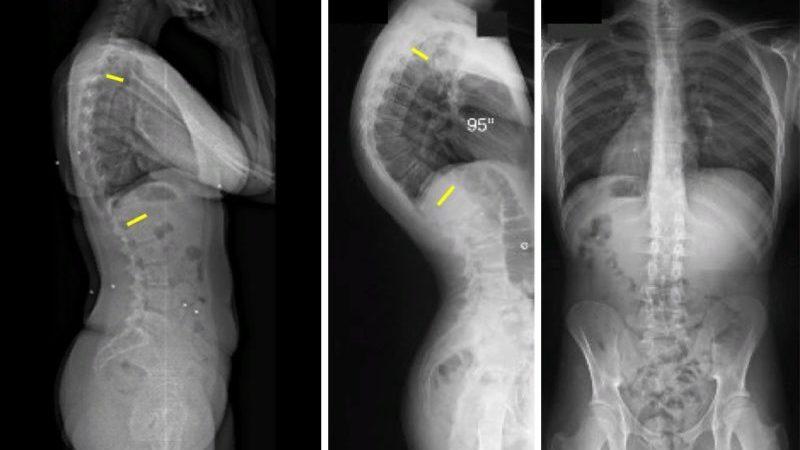

На поздних стадиях заболевания у ребенка формируется плоская спина, грудная клетка деформируется и принимает воронкообразную форму. Серьезным симптомом на поздних этапах являются неврологические расстройства. Также у пациента может наблюдаться деформация голеней.

Основным способом диагностики данного заболевания является рентгенологическое исследование. Оно позволяет определить:

- ротацию позвонков в грудном и поясничном отделах;

- наличие клиновидной деформации позвонков;

- наличие грыжи Шморля.